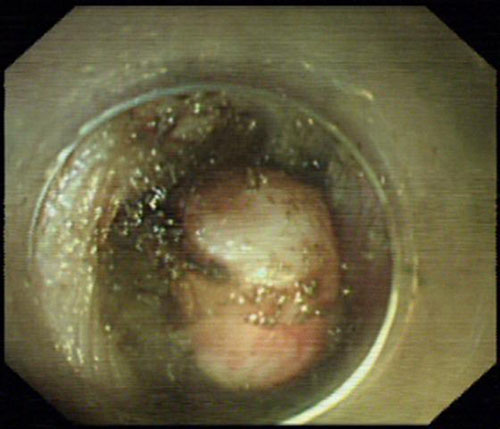

内镜见食管中段肿瘤

患者男性,52岁,电子胃镜见食管中段一大小约1.8x1.5cm肿物,超声内镜提示起源于食管固有肌层,传统的治疗方法一般建议外科开胸手术,但其创伤大,费用高,恢复期长,也降低了患者生活质量。消化内科赵赛菊、杨力主任基于近年来科室在内镜治疗技术上的长足发展和丰富的临床经验,仔细研究了患者的病情和影像学资料,在取得患者的知情同意后,决定采用当今最新的内镜治疗技术——经内镜粘膜下隧道肿瘤切除术(STER)为患者切除肿瘤。